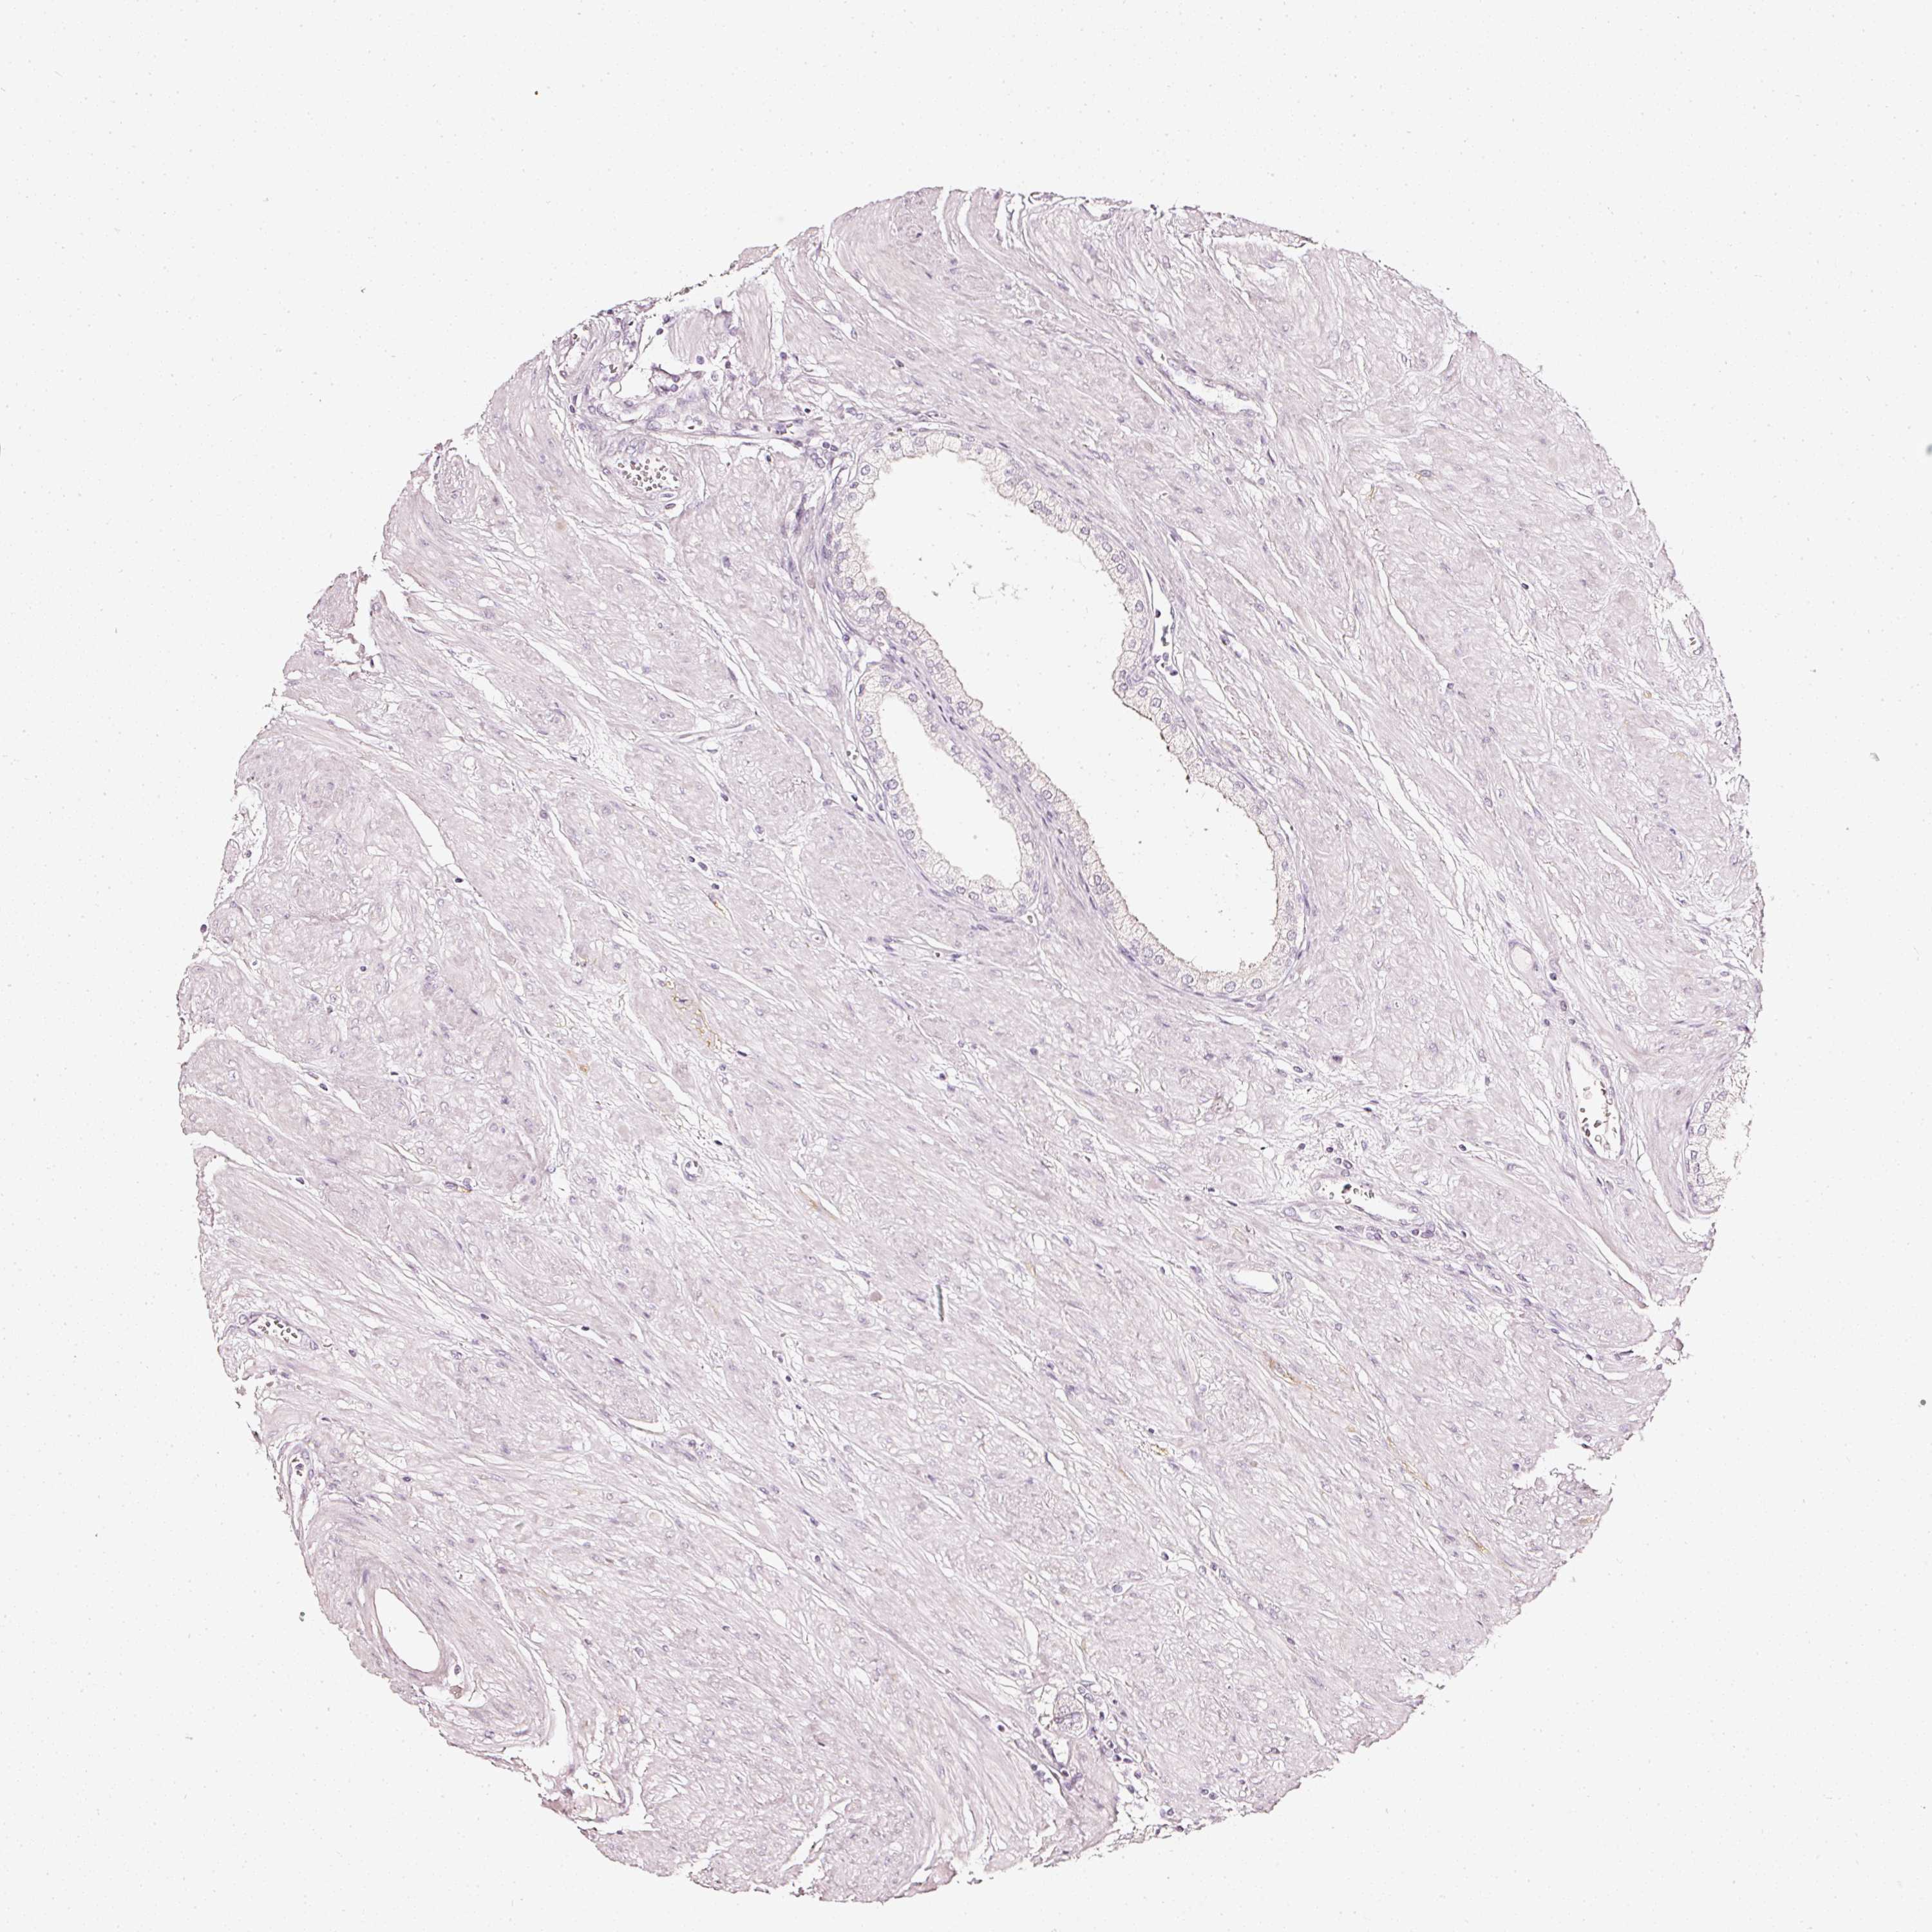

PROSTATE CANCER - Protein expressioni

A mouse-over function shows sample information and annotation data. Click on an image to view it in a full screen mode. Samples can be filtered based on level of antibody staining by selecting one or several of the following categories: high, medium, low and not detected. The assay and annotation is described here.

Antibody stainingi

Antibody staining in the annotated cell types in the current human tissue is reported as not detected, low, medium, or high, based on conventional immunohistochemistry profiling in selected tissues. This score is based on the combination of the staining intensity and fraction of stained cells.

Each image is clickable and will lead to virtual microscopy that enables deeper exploration of all samples and also displays staining intensity scores, fraction scores and subcellular localization as well as patient and tissue information for each sample.

HPA023266

HPA023278

HPA023280

HPA023338

CAB002672

Staining

High

Medium

Low

Not detected

Intensity

Strong

Moderate

Weak

Negative

Quantity

>75%

75%-25%

<25%

None

Location

Nuclear

Cytoplasmic/membranous

Cytoplasmic/membranous,nuclear

Adenocarcinoma, High grade

Adenocarcinoma, Low grade

Adenocarcinoma, NOS

Adenocarcinoma, Medium grade